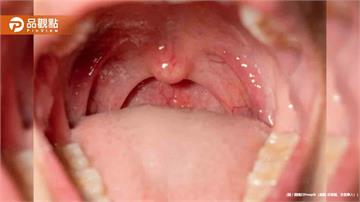

「嘴裡沙沙的」冒粗糙顆粒! 老司機靠檳榔提神驚現癌變徵兆